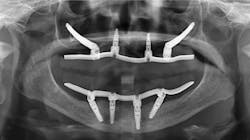

This next situation is a very common one when observing the current trend to oppose zirconia restorations on two edentulous arches without meticulous and knowledgeable occlusal equilibration. This can cause an implant or two to take the entire occlusal load, causing undue forces and stress on theAfter many decades of prosthodontic practice and hundreds of rehabs, I have found this an almost impossible and threatening technique. There is no articulator that can consistently mimic patient occlusion. Definitive occlusal equilibration is mandatory at seating, after a few weeks in the mouth, and subsequently on recare appointments (figures 4–6).